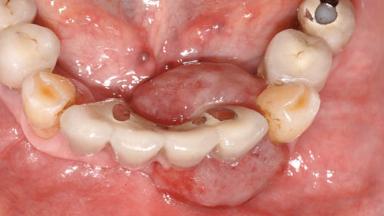

Peripheral Giant-cell Granuloma Associated with Peri-implant Tissues

Jaw Mandible

Area Anterior|Posterior

# of Teeth 10

# of Implants 5